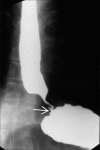

Recent years have seen a decline in number of barium procedures due to wider availability of cross sectional imaging modalities. Though use of barium esophagography/barium swallow has decreased in day to day clinical practice, it still remains a valuable test for structural and functional evaluation of esophagus. It can be performed as single or double contrast examination or as a multiphasic examination comprising upright double contrast views followed by prone single contrast views. This pictorial essay demonstrates imaging features of various esophageal diseases on barium esophagogram.